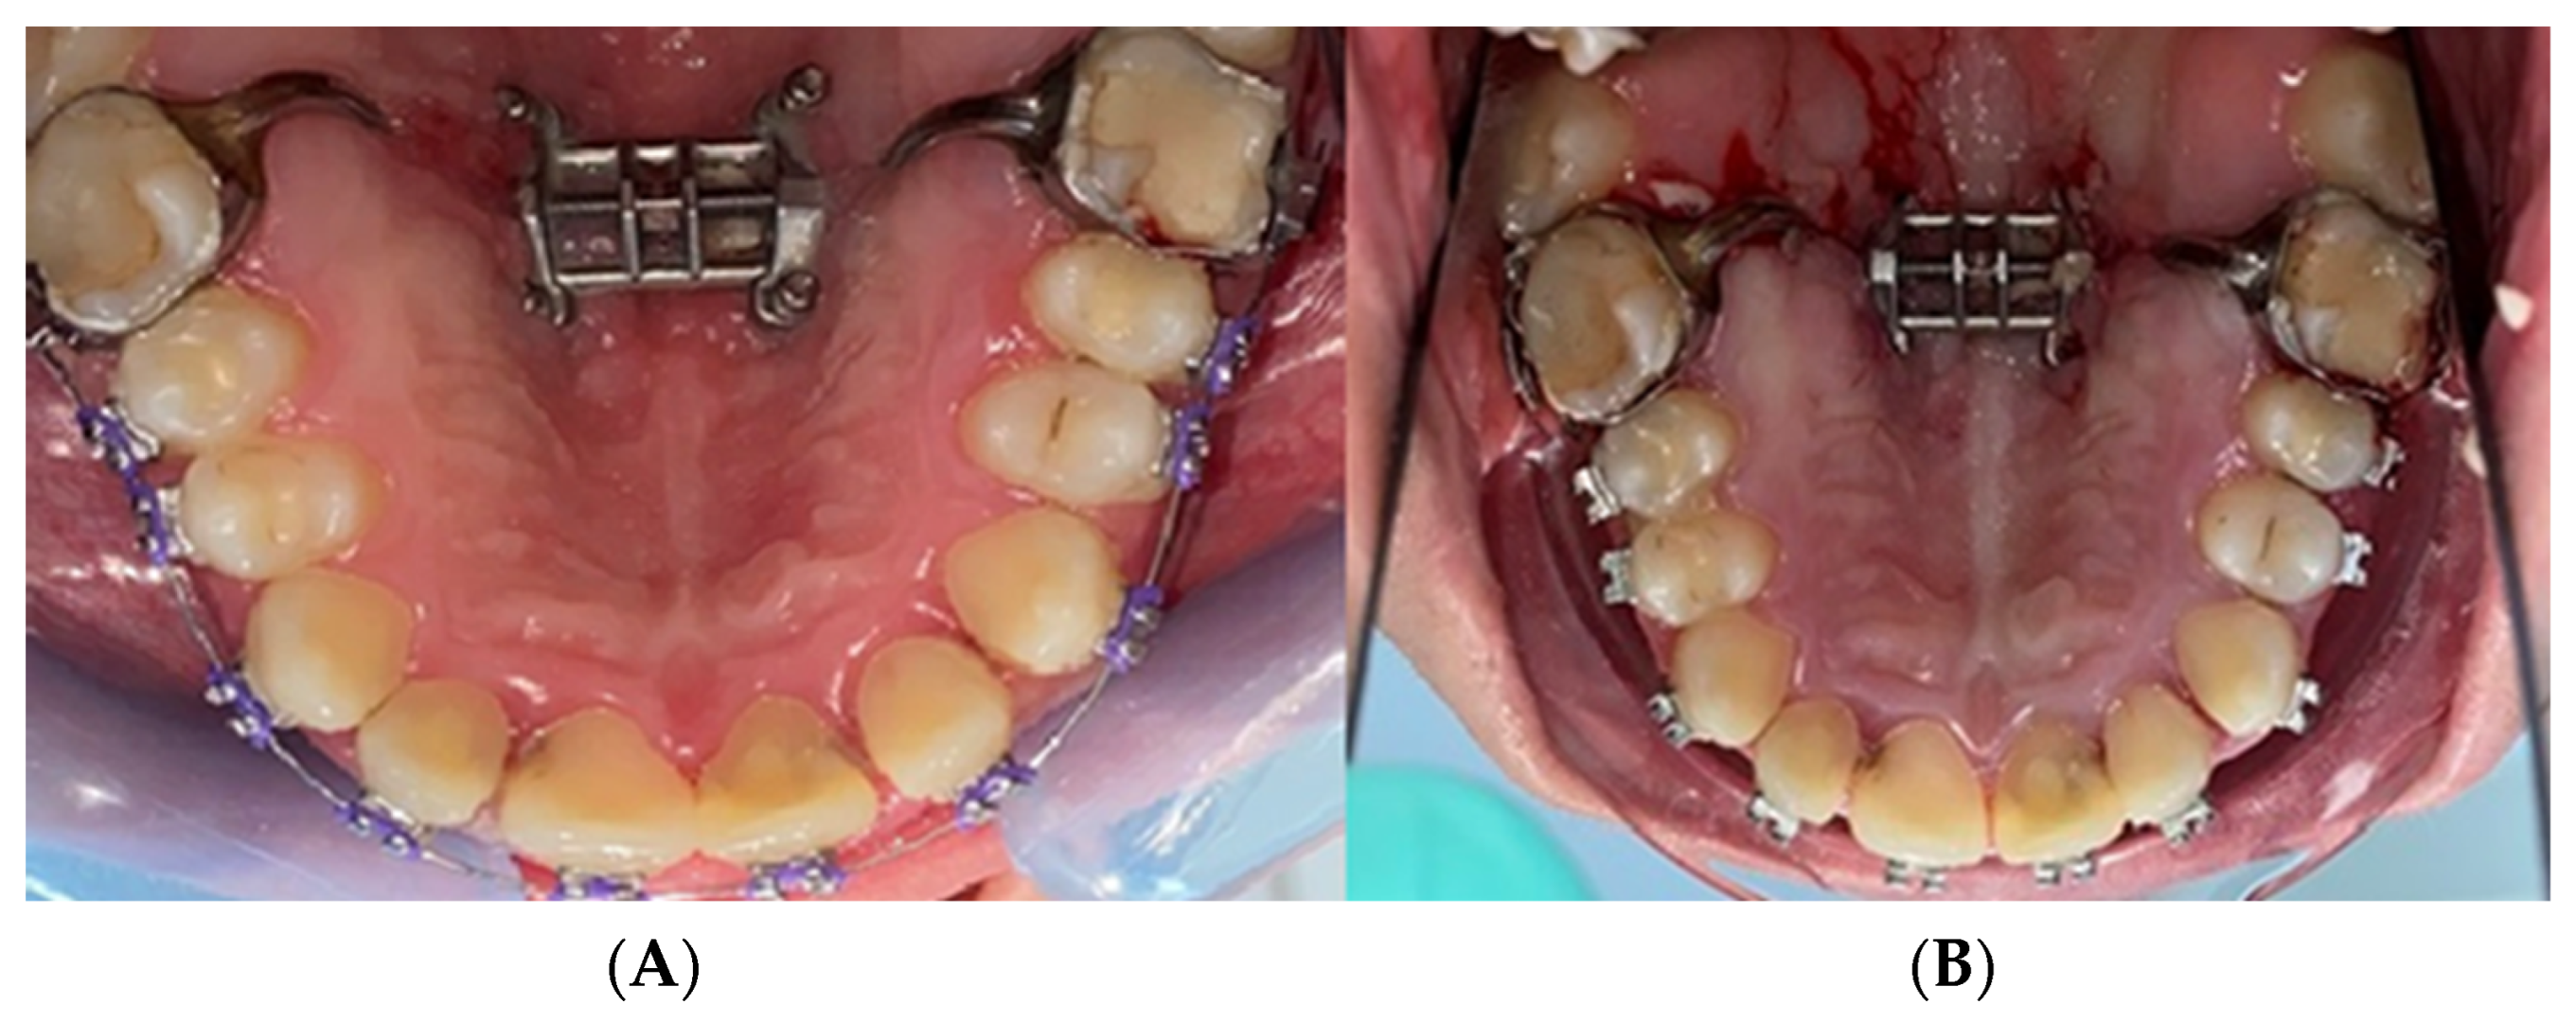

2.2. Palatal Expander Placement

2.3. Assessment of the Study Group

3. Results